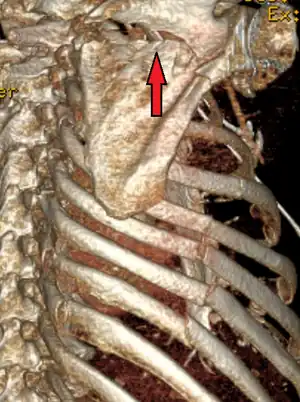

a)Axial computed tomography showing- bilateral scapular fractures (bilateral pulmonary contusion, left haemothorax) b) 3D computed tomography reconstruction shows bilateral scapular body fractures -